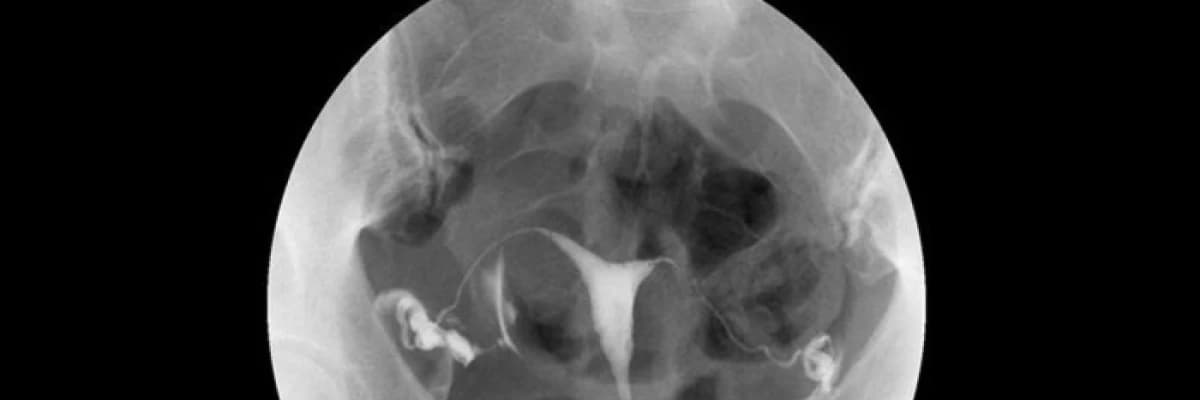

Histerosalpingografi (HSG) veya Türkçe deyişle rahim filmi jinekolojide rahim içinin ve kanalların yapısal ve işlevsel özelliklerini incelemede kullanılan bir yöntemdir. İnfertilite (kısırlık) değerlendirmesinde istenen temel testlerden birisidir. Ayrıca rahim ağzına veya rahme uygulanan bir müdahale sonrasında (kürtaj gibi) adet kanamalarının kesilmesi ya da çok azalması durumunda rahim ağzı kanalındaki muhtemel bir tıkanıklığın veya rahim içerisindeki muhtemel bir yapışıklığın (Asherman sendromu) değerlendirilmesinde, tekrarlayan düşüklerde rahimde doğumsal bir gelişim kusuru bulunup bulunmadığının (aşağıda soldaki resim - bölmeli rahim) belirlenmesinde de yaygın olarak kullanılır.

Rahim filmi bir Kadın Hastalıkları ve Doğum Uzmanı ve Radyoloji Uzmanı veya Teknisyeni tarafından beraberce uygulanır. Jinekolojik muayene pozisyonundayken rahim ağzını görüntülemek için vajinaya alet yerleştirilir. Daha sonra rahme kanül adı verilen bir diğer alet yerleştirilir. Kanüle tutturulan enjektörden birkaç aşamada basınç uygulanarak kontrast madde (ilaçlı madde) verilir. Bu sıvı röntgen filminde bulunduğu yerlerde ışını geçirmediğinden beyaz bir görünüm kazandırır. Sıvı verilmesi esnasında ya belli aralıklarla röntgen filmleri alınır veya floroskopi adı verilen yöntem kullanılarak ekrandan sıvının geçişi sürekli olarak izlenir ve kaydedilir. Böylelikle rahmin içyapısı, kanalların açık olup olmadığı ve yapıları değerlendirilir. HSG, röntgen ışınları yardımıyla gerçekleştirilen bir teknik olmasına karşın verilen ışın dozu yüksek değildir.